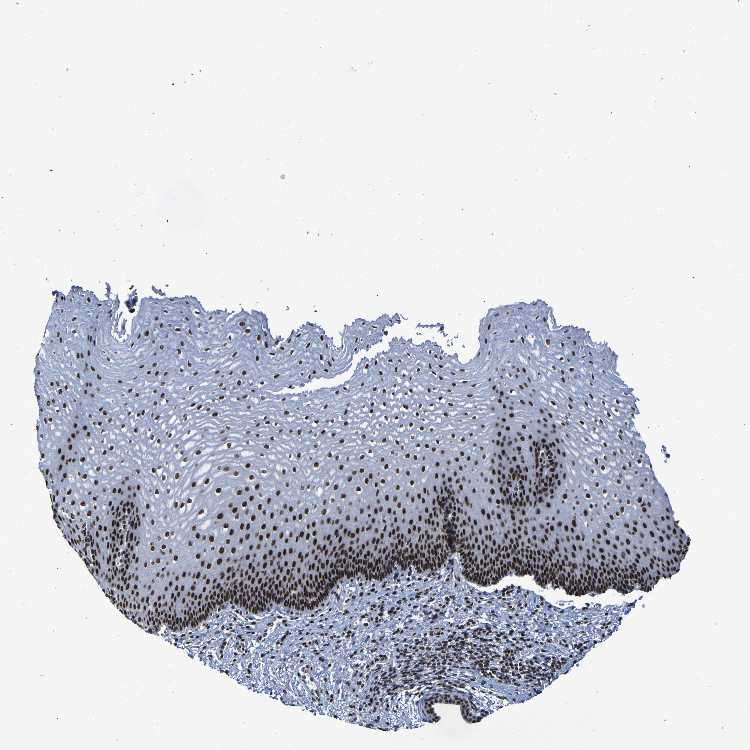

TISSUE PRIMARY DATA ESOPHAGUS Show tissue menu

ESOPHAGUS - Antibody stainingi

Antibody staining in the annotated cell types in the current human tissue is reported as not detected, low, medium, or high, based on conventional immunohistochemistry profiling in selected tissues. This score is based on the combination of the staining intensity and fraction of stained cells.

Each image is clickable and will lead to virtual microscopy that enables deeper exploration of all samples and also displays staining intensity scores, fraction scores and subcellular localization as well as patient and tissue information for each sample.

Antibody HPA026092Antibody CAB011687

Squamous epithelial cells HighHigh